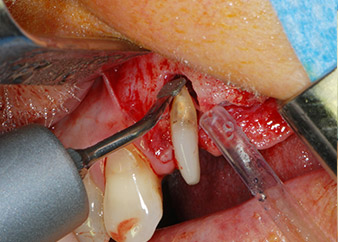

buccal apex of tooth 24

Fig 5: ... and the buccal apex of tooth 24 was abraded with the same instrument (apicoectomy).

Then the apex was abraded with the same instrument to remove residual infected apical tissue and to reduce possible accessory root-canal ramifications (apicoectomy) (Fig. 5). A retrograde filling was not necessary because the orthograde filling had just been revised.